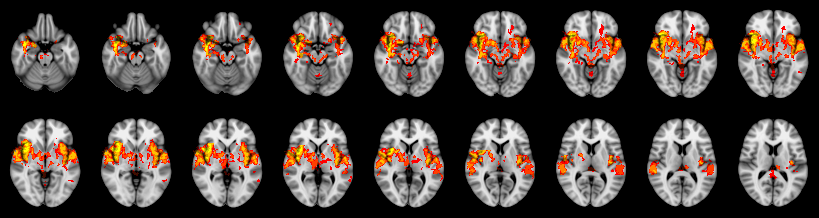

Pain study, TFCE, Corrected

Not combined

Face:

Hand:

Foot: